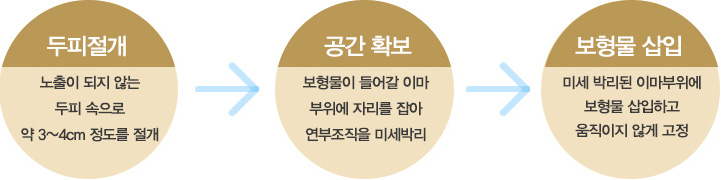

탑클래스성형외과에서는 개인별 이마의 모양과 크기가 다르기 때문에 1:1 맞춤형 이마석고 모형을 본 떠 보형물을

준비합니다. FDA 승인을 받은 보형물의 사용으로 안전하며, 이물감이 적고 염증 유발의 걱정이 적습니다.